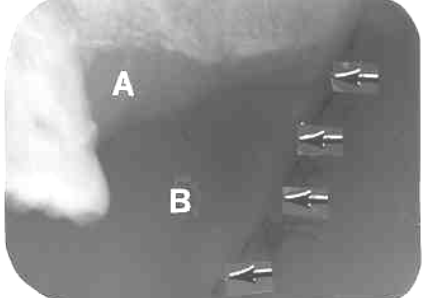

3. What is the anatomical structure indicated by arrow in this radiograph?